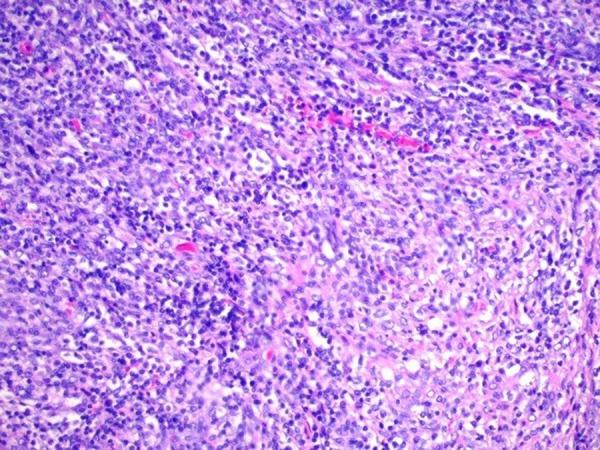

BACKGROUND Granulocytic sarcoma, or 'chloroma,' due to extramedullary acute myeloid leukemia (AML) or due to acute myelomonocytic leukemia (AML M5), is rare and is associated with a poor prognosis. This report is of a case of granulocytic sarcoma of the gallbladder and describes the approach to diagnosis and treatment. CASE REPORT A 74-year-old Hispanic woman from Ecuador presented to the emergency department with a five-day history of fever, jaundice, and right upper quadrant abdominal pain. The right upper quadrant ultrasound showed a thickened gallbladder wall with cholelithiasis, a positive sonographic Murphy sign, and marked dilatation of the common bile duct, which was up to 17 mm in diameter. Endoscopic retrograde cholangiopancreatography (ERCP) showed purulence and a stone in the common bile duct, which was removed. She underwent laparoscopic cholecystectomy which identified gangrenous cholecystitis. Despite cholecystectomy and treatment with broad-spectrum antibiotics, she remained febrile with a leukocytosis of up to 80,000 cells/µL. Histopathology of the gallbladder showed infiltrating myeloblasts within the mucosa, submucosa, and muscularis consistent with a granulocytic sarcoma associated with gangrenous cholecystitis due to cholelithiasis. Immunohistochemistry, using a panel of antibodies to CD33, CD68, HLA-DR, and lysozyme, supported the diagnosis of granulocytic sarcoma or extramedullary acute myelomonocytic leukemia (AML M5). CONCLUSIONS A rare case of an extramedullary hematologic malignancy, granulocytic sarcoma of the gallbladder is presented, which highlights the importance of timely diagnosis and treatment, due to the high mortality rate associated with granulocytic sarcoma, or extramedullary AML.

背景